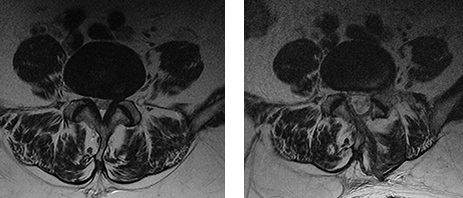

자기공명영상 검사 (MRI)

가장 정확한 검사법으로 추간판 탈출 정도나 척추의 손상 및 신경의 압박 정도, 인대 근육 등의 조직 손상까지 확인이 가능합니다.